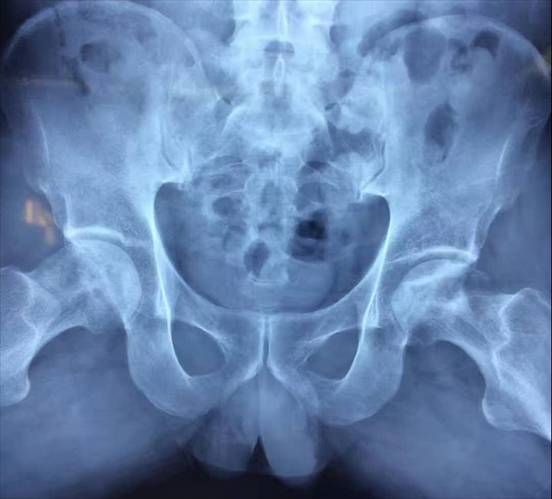

术前术后对比

全膝关节翻修术

全髋关节翻修术